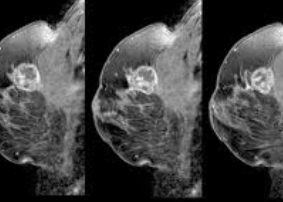

유방암은 유방에 생기는 암입니다.

유방에 있는 세포들이 비정상적으로 빠르게 자라면서 종양을 만들고, 이 종양이 몸에 퍼질 수 있는 병이죠.

유방암은 초기에 발견하면 치료가 용이하지만, 발견이 늦어지면 치료가 어려울 수 있어서 정기적인 검사가 중요합니다. 😢